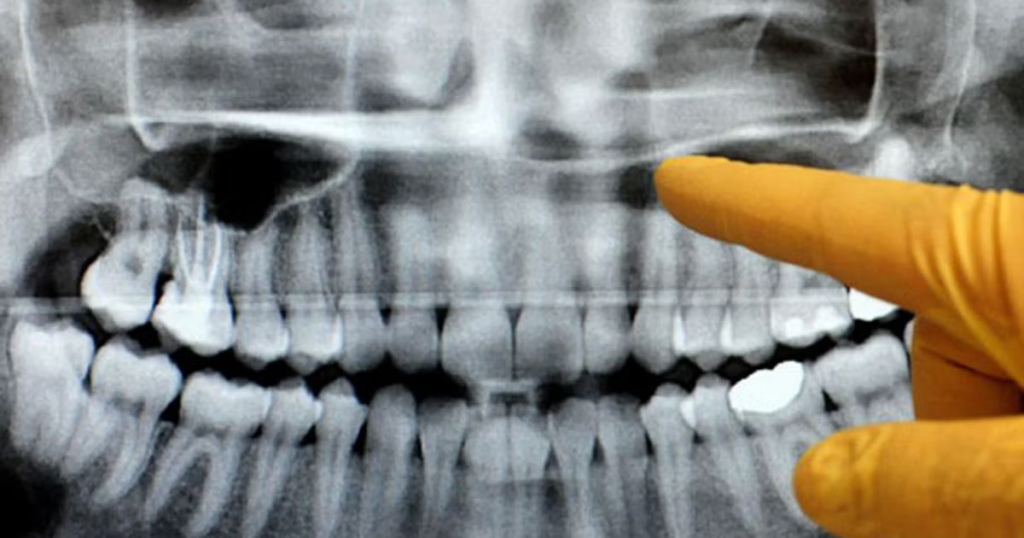

Dental x-rays are an important part of maintaining your oral health. They allow your dentist to see what the naked eye can’t, especially with certain procedures. With x-rays, we can plan treatments more accurately, and keep your smile healthy for the long term.

Klinik Pergigian Shakirin comes equipped with a CBCT machine. Unlike traditional X-rays, a CBCT scan provides a detailed 3D view of your teeth, jawbone, nerves, and surrounding structures. This technology helps in finding issues like bone loss or impacted teeth, as well as planning for treatments like dental implants, orthodontics, and wisdom tooth extractions.

Even with the most careful visual exam, your dentist can only see what’s on the surface. Many dental problems start quietly beneath the enamel, in the roots, or even in the bone. Some of the hidden issues x-rays can reveal include:

Cavities between teeth – Tooth decay often begins in tight spaces where a mirror or probe can’t reach. By the time you feel pain, the cavity may already be deep.

Infections in the root or bone – An x-ray can spot signs of abscesses or infections long before they become painful or spread further.

Bone loss from gum disease – Gum disease doesn’t just affect your gums. Over time, it can weaken the jawbone that supports your teeth. X-rays help track this early.

Impacted wisdom teeth – Wisdom teeth that grow sideways or remain trapped under the gums can cause pain, infection, or crowding. X-rays show their exact position.